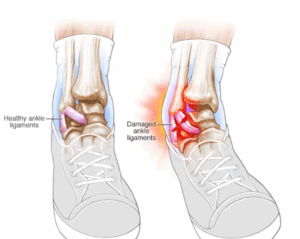

Sprained ankle

A sprained ankle is an injury that occurs when you roll, twist or turn your ankle in an awkward way. This can stretch or tear the tough bands of tissue (ligaments) that help hold your ankle bones together.

Sprains

A sprain is a stretching or tearing of ligaments — the tough bands of fibrous tissue that connect two bones together in your joints. The most common location for a sprain is in your ankle.